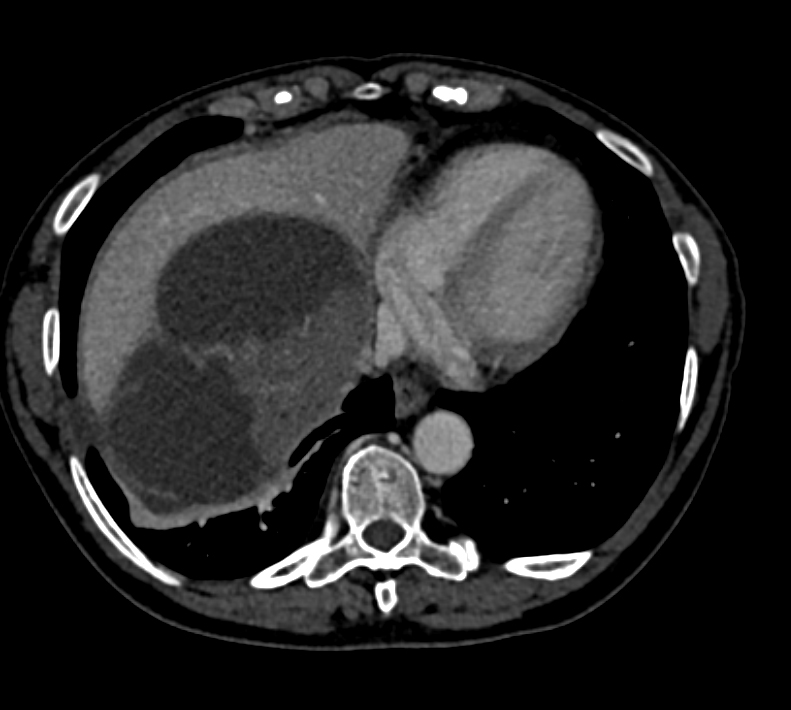

5) In this hypertensive patient the best diagnosis is?

bladder cancer

pheochromocytoma

bladder polyp

multifocal TCC